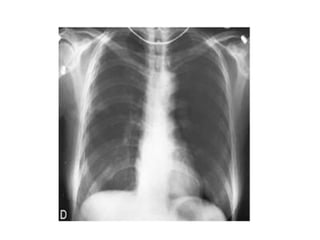

RADIOGRAPHICDIAGNOSIS

1- CXR

The standard procedure in making the diagnosis.

 It should be upright and preferably in the posteroanterior

projection. It is possible to miss a pneumothorax in a

semisupine portable anteroposterior view. If the patient

cannot be upright, a lateral decubitus view with the suspect

side positioned up may be helpful.